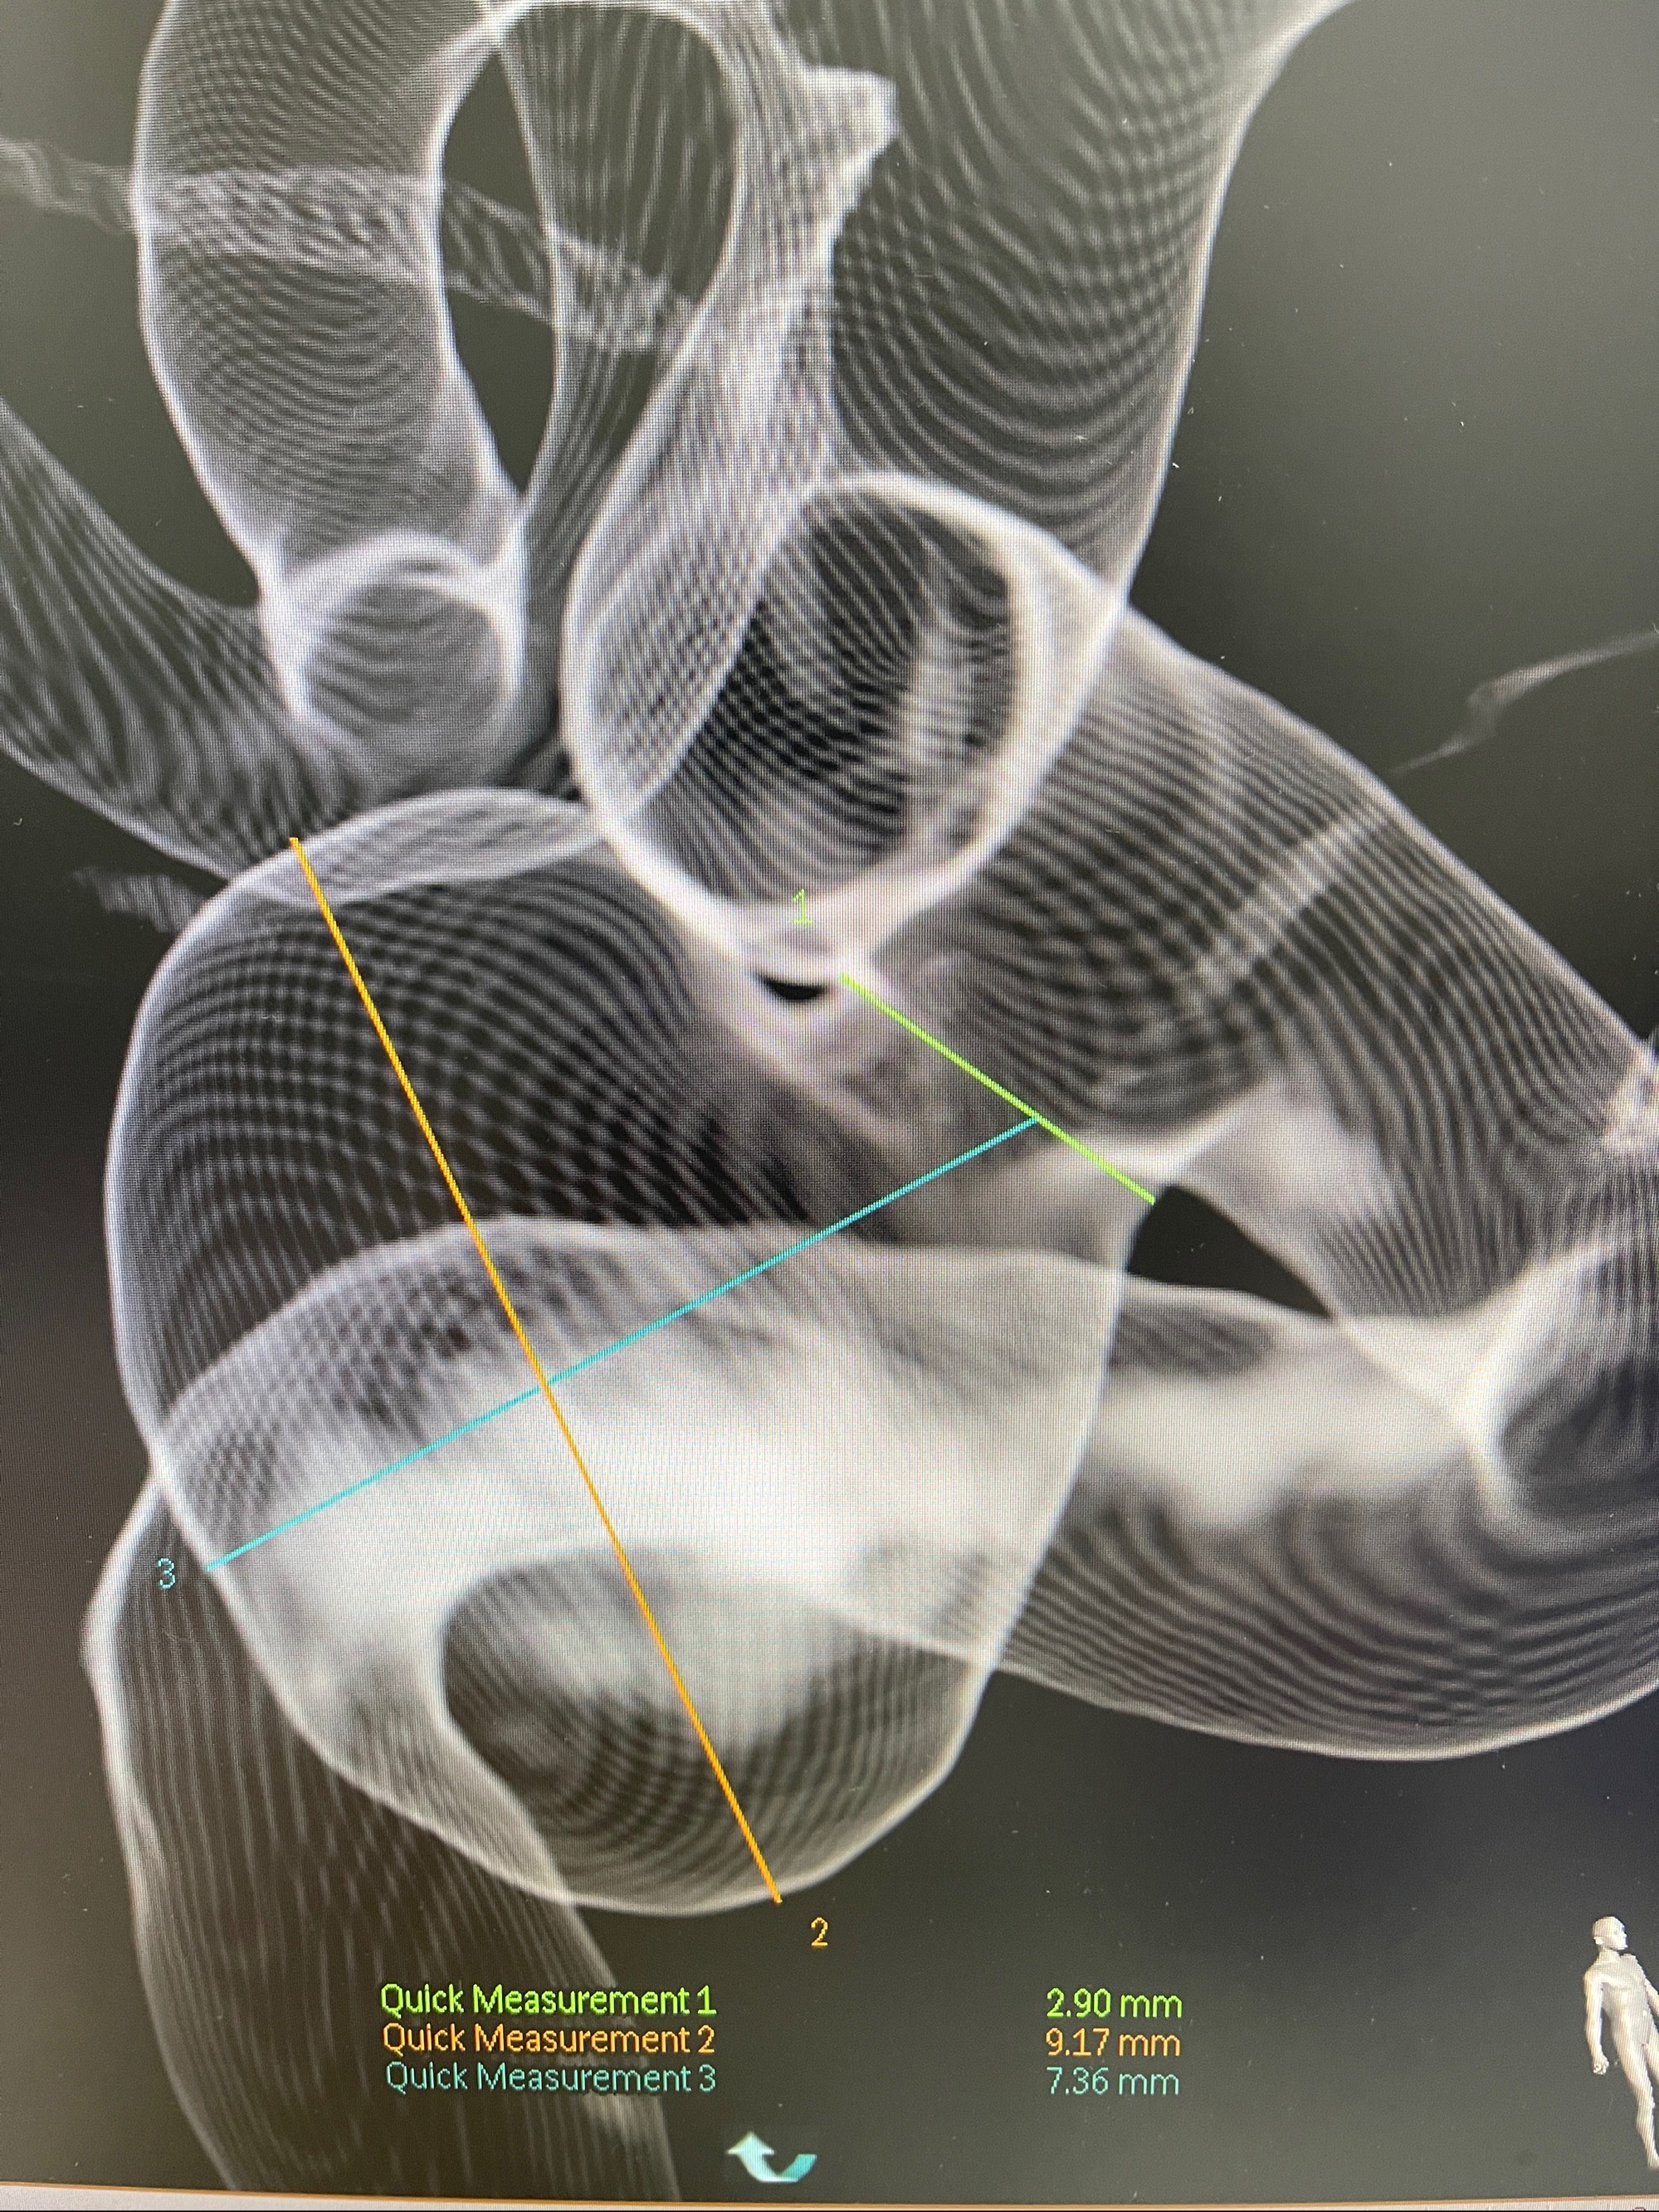

2023-08-30DSA:左侧颈内动脉眼动脉动脉瘤,约3*9.2*7.3mm大小

术后3D显示支架贴壁佳